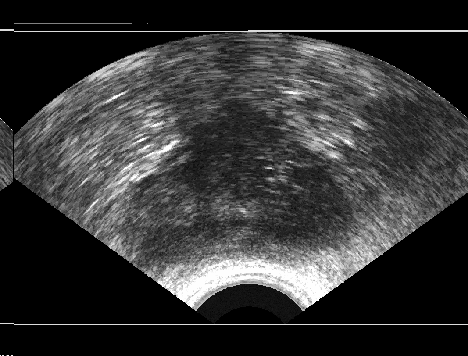

IV-A Image Data: Synthetic TRUS Images

It is a considerable challenge to validate any approach to computed consensus contouring. The ultimate test, to be sure, is to measure the accuracy of the computed consensus contour 𝐂𝐂\mathbf{C}. However, this depends on assessing the quality of the consensus. Unless there is a “gold-standard segment” G𝐺G for each image, reliable validation will not be straightforward, and any particular observation will be inconclusive. Of course, this is not feasible with real images, for which there is no gold standard. Hence, we generated synthetic images whose gold segments were known a priori. For this reason, we used synthetic images that simulate transrectal ultrasound (TRUS) images.

TRUS images of prostates may be used to both diagnose and treat prostate diseases such as cancer. Starting with a set of prostate shapes P1,P2,,Pmsubscript𝑃1subscript𝑃2subscript𝑃𝑚P_{1},P_{2},\dots,P_{m}, we created random segments Gisubscript𝐺𝑖G_{i} through combinations of those priors, adding noise along with random translations and rotations, and we distorted the results with speckle noise and shadow patterns. Each image Iisubscript𝐼𝑖I_{i} is thus created from its gold Gisubscript𝐺𝑖G_{i}. Consequently, we can simulate k𝑘k user delineations Si1,Si2,,Siksuperscriptsubscript𝑆𝑖1superscriptsubscript𝑆𝑖2superscriptsubscript𝑆𝑖𝑘S_{i}^{1},S_{i}^{2},\dots,S_{i}^{k} by manipulating Gisubscript𝐺𝑖G_{i} via scaling, rotation, and morphological changes, and we can simulate edits by running active contours with variable user-simulating parameters. The variability of user delineations was simulated according to several factors: error probability ([0,0.05]00.05[0,0.05]), anatomical difficulty (=0.2absent0.2=0.2 out of [0,1]01[0,1]), and the scaling factor for morphology (form 1×1111\!\times\!1 to 21×21212121\!\times\!21). The user was modelled according to the level of experience (a random number from (0,1]01(0,1]), the user’s attention (a random number from [0,1]01[0,1]), and the user’s tendencies in terms of the segment size (a random number from [1,1]11[-1,1]), whether tending to draw contours that are relatively small (1absent1\rightarrow\!-1) or large (+1absent1\rightarrow\!+1).

We generated 500 images from their corresponding gold-standard images. Furthermore, we generated 20 different segments for each image, assuming that there were 20 users. Figure 4 shows three examples of real and synthetic TRUS images. One should bear in mind that the purpose here was not to simulate the images realistically, but rather to have a base from which to generate variable segments from a perfect segment. Figure 5 shows an example of the gold segments and simulated user contours. The variability, coupled with the gold segment, is what is needed to validate our approach.

Figure 4: Sample TRUS (top) and simulated images (bottom).